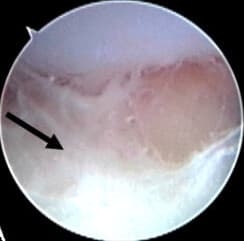

Acute septic arthritis, infectious arthritis, suppurative arthritis, pyogenic arthritis, osteomyelitis, or joint infection is the invasion of a joint by an infectious agent resulting in joint inflammation. Generally speaking, symptoms typically include redness, heat and pain in a single joint associated with a decreased ability to move the joint. Onset is usually rapid. Other symptoms may include fever, weakness and headache. Occasionally, more than one joint may be involved, especially in neonates, younger children and immunocompromised individuals. In neonates, infants during the first year of life, and toddlers, the signs and symptoms of septic arthritis can be deceptive and mimic other infectious and non-infectious disorders. In children, septic arthritis is usually caused by non-specific bacterial infection and commonly hematogenous, i.e., spread through the bloodstream. Septic arthritis and/or acute hematogenous osteomyelitis usually occurs in children with no co-occurring health problems. Other routes of infection include direct trauma and spread from a nearby abscess. Other less common cause include specific bacteria as mycobacterium tuberculosis, viruses, fungi and parasites. In children, however, there are certain groups that are specifically vulnerable to such infections namely preterm infants, neonates in general, children and adolescence with hematologic disorders, renal osteodystrophy and immune-compromised status. In adults vulnerable groups include an artificial joint, prior arthritis, diabetes and poor immune function. Diagnosis is generally based on accurate correlation between history-taking and clinical examination findings and basic laboratory and imaging findings like joint ultrasound. In children septic arthritis can have serious consequences if not treated appropriately and timely. Initial treatment typically includes antibiotics such as vancomycin, ceftriaxone or ceftazidime. Surgery in the form of joint drainage is the gold standard management in large joints like the hip and shoulder.